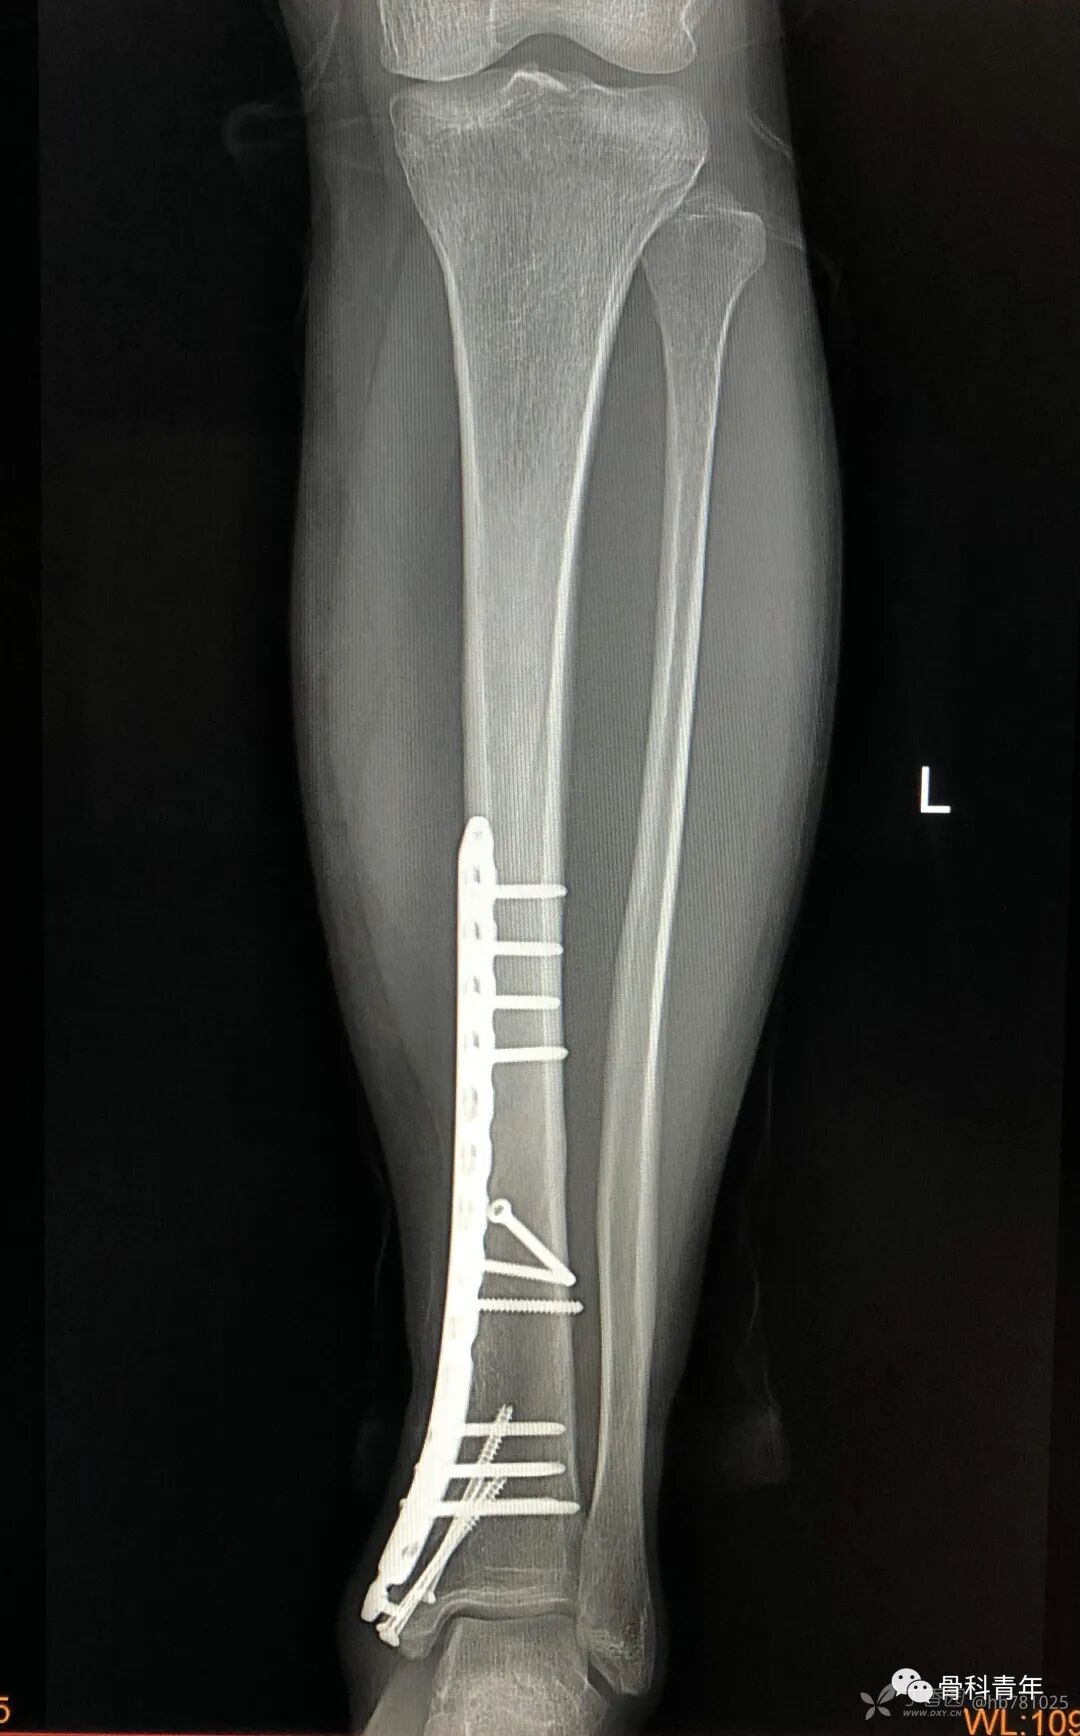

11.胫骨下段伴内踝骨折